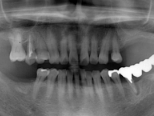

症例写真(レントゲン)